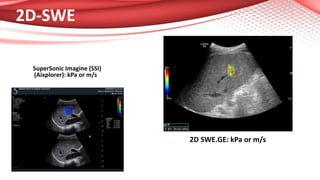

2D-SWE

SuperSonic Imagine (SSI)

(Aixplorer): kPa or m/s

2D SWE.GE: kPa or m/s

Ultrasound based LiverElastography • Shear Wave Elastography (SWE) methods are implemented in ultrasound machines. • Point SWE (VTQ-Siemens and ElastPQ-Philips) or 2D-SWE (SSI-Aixplorer, 2D- SWE.GE-General Electric, Toshiba, Philips and others) can perform numeric evaluation of liver stiffness in less than 5 minute. • Results are expressed in kilopascals or meters/second. • Good clinical results for all this systems!

2D-SWE SuperSonic Imagine (SSI) (Aixplorer):kPa or m/s 2D SWE.GE: kPa or m/s